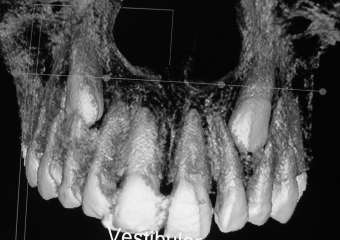

Tomografia - Caninos inclusos e intra-ósseos - Clínica Cliniface

Tomografia - Caninos inclusos e intra-ósseos